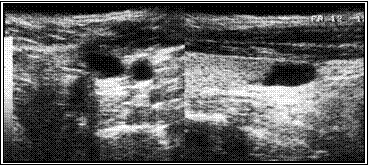

Ниже иллюстрируется клинических случай больной Л, 18 лет. При УЗИ в левой доле обнаружен кистозно-дегенерированный узел 21х9х15 мм. Кистозная дегенерация составила около 75% от объема. При диагностической тонкоигнольной пункционной биопсии дважды получены клетки фолликулярного эпитерия щитовидной железы (кубического и пролиферирующего) и элементы пунктата кистозной полости.

На приведенных ниже эхограммах демонтрируется динамика регрессии в течение года.

А. Эхограмма до склеротерапии

Б. Эхограмма через три месяца после склеротерапии

В. Эхограмма через год после склеротерапии. Полная регрессия узла.